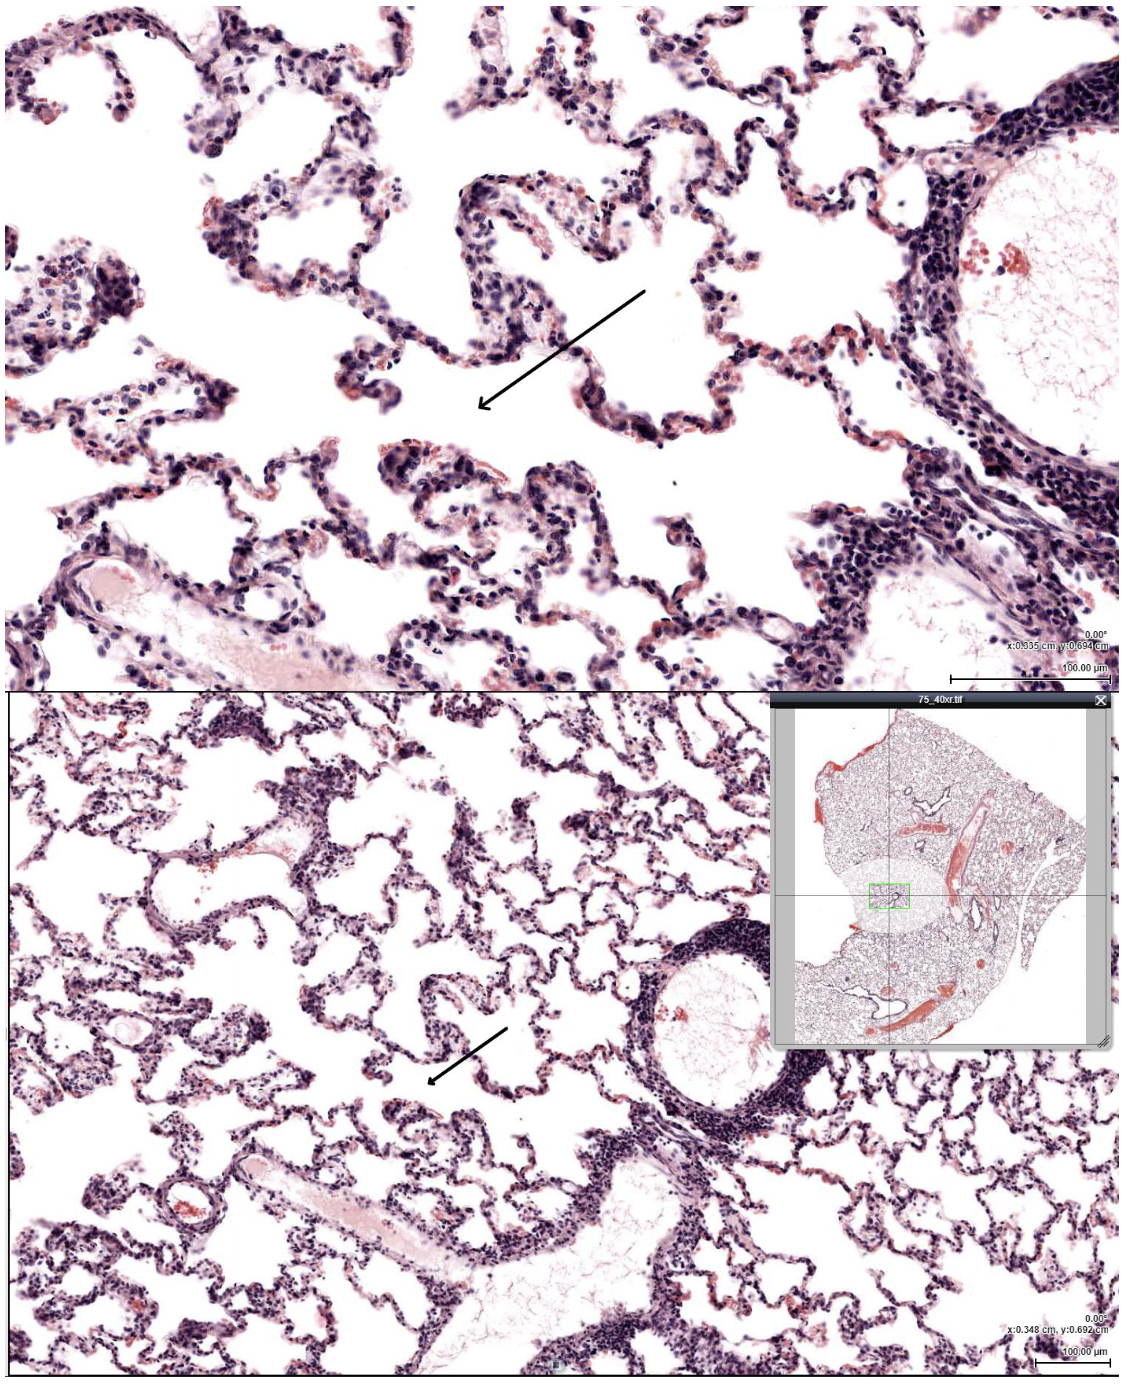

A 68-year-old man with a 45–pack-year smoking history presents with progressive exertional dyspnea. Pulmonary function testing shows increased total lung capacity and decreased DLCO. Histologic examination of lung tissue using H&E and elastic fiber staining reveals permanent enlargement of air spaces distal to the terminal bronchioles with destruction of alveolar septa. Which of the following mechanisms is most responsible for these findings?

Protease–antiprotease imbalance leading to elastin degradation

A 62-year-old male presents with chronic productive cough for at least 3 months per year for the past 2 consecutive years. Arterial blood gas analysis shows hypercapnia. Bronchial biopsy stained with H&E demonstrates mucous gland enlargement and increased goblet cells. Which histopathologic finding is most characteristic of this condition?

Increased Reid index greater than 50%